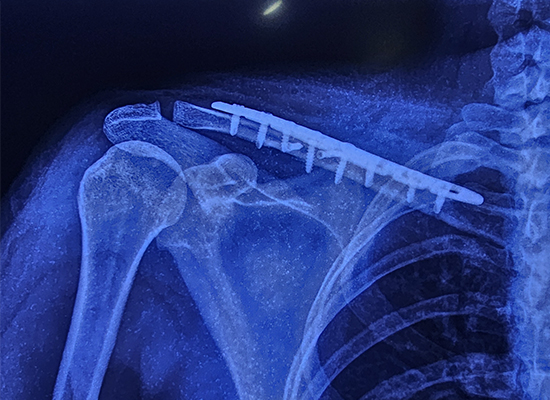

La cirugía implicó el uso de una placa de bloqueo de clavícula en S especializada, un implante avanzado diseñado para proporcionar estabilidad en fracturas multifragmentadas. Se eligió la placa de 8 orificios debido a su ajuste preciso y su capacidad para soportar la fractura durante el proceso de curación. La operación transcurrió sin problemas y no surgieron complicaciones durante el procedimiento.

El paciente fue dado de alta apenas 24 horas después de la cirugía, lo que demuestra la eficacia del tratamiento. Las imágenes tomadas seis semanas después de la cirugía mostraron que la fractura había sanado por completo y la paciente pudo reanudar sus actividades diarias sin molestias. Esta rápida recuperación resalta las ventajas del uso de implantes modernos como la placa de bloqueo de clavícula en S en cirugías ortopédicas.

Tipo de implante: placa de bloqueo de clavícula en S

Tamaño : 8 agujeros, lado derecho

Material: aleación de titanio para mayor resistencia y durabilidad.

El contorno en forma de S se adapta a la anatomía de la clavícula, distribuyendo la tensión de manera uniforme y evitando que el implante se afloje o migre.